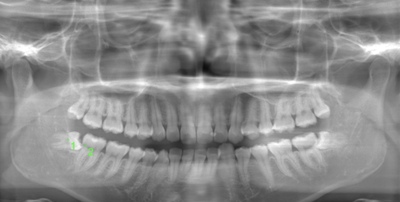

CASE 1

基本情報

| 年齢・性別 | 30代・女性 |

| 主訴 | 左右に分けて親知らずを抜きたい、できれば痛くなく抜きたい |

| 親知らずのはえ方 | 完全に出ていてまっすぐはえている |

| 抜歯期間 | 15分 |

| 抜歯費用 | 約2,000円(保険内) |

| 抜歯内容 |

何度か虫歯になり痛みはないが早めに抜きたい。 完全に頭が出ているため歯ぐきを切ったり骨を削らずに抜歯しました。 根の形も単純なため抜歯自体は5分もかからず上下ともに終わりました。 術後痛みや腫れも出ていません。 抜歯後は感染をしやすいため必ず抗生物質を飲み切ってください。 |